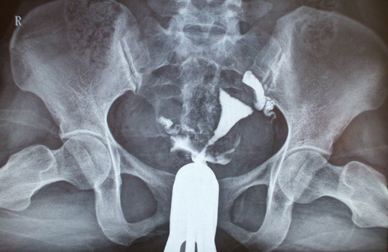

第三代试管婴儿技术基因筛选的原理,植入前遗传学诊断(PGD),可以判断一个胚胎是否正常与异常,某些染色体异常,如唐氏综合症。试管婴儿PGD筛查需要在胚胎活检第3天或5,其中一个细胞是从胚胎中剥除,是固定的DNA和细胞的结构分析。从3天的胚胎成长到5天或6胚胎的胚胎留在孵化器内的试管婴儿实验室,验室接收结果从PGD实验室的胚胎是正常的,什么性别的胚胎。然后可以决定对胚胎转移和冻结。显然,诊断为异常的胚胎不会被用于胚胎移植。胚胎植入前诊断的结果是非常成功的,如果怀孕大约有99%-100%获得所需性别的机会。